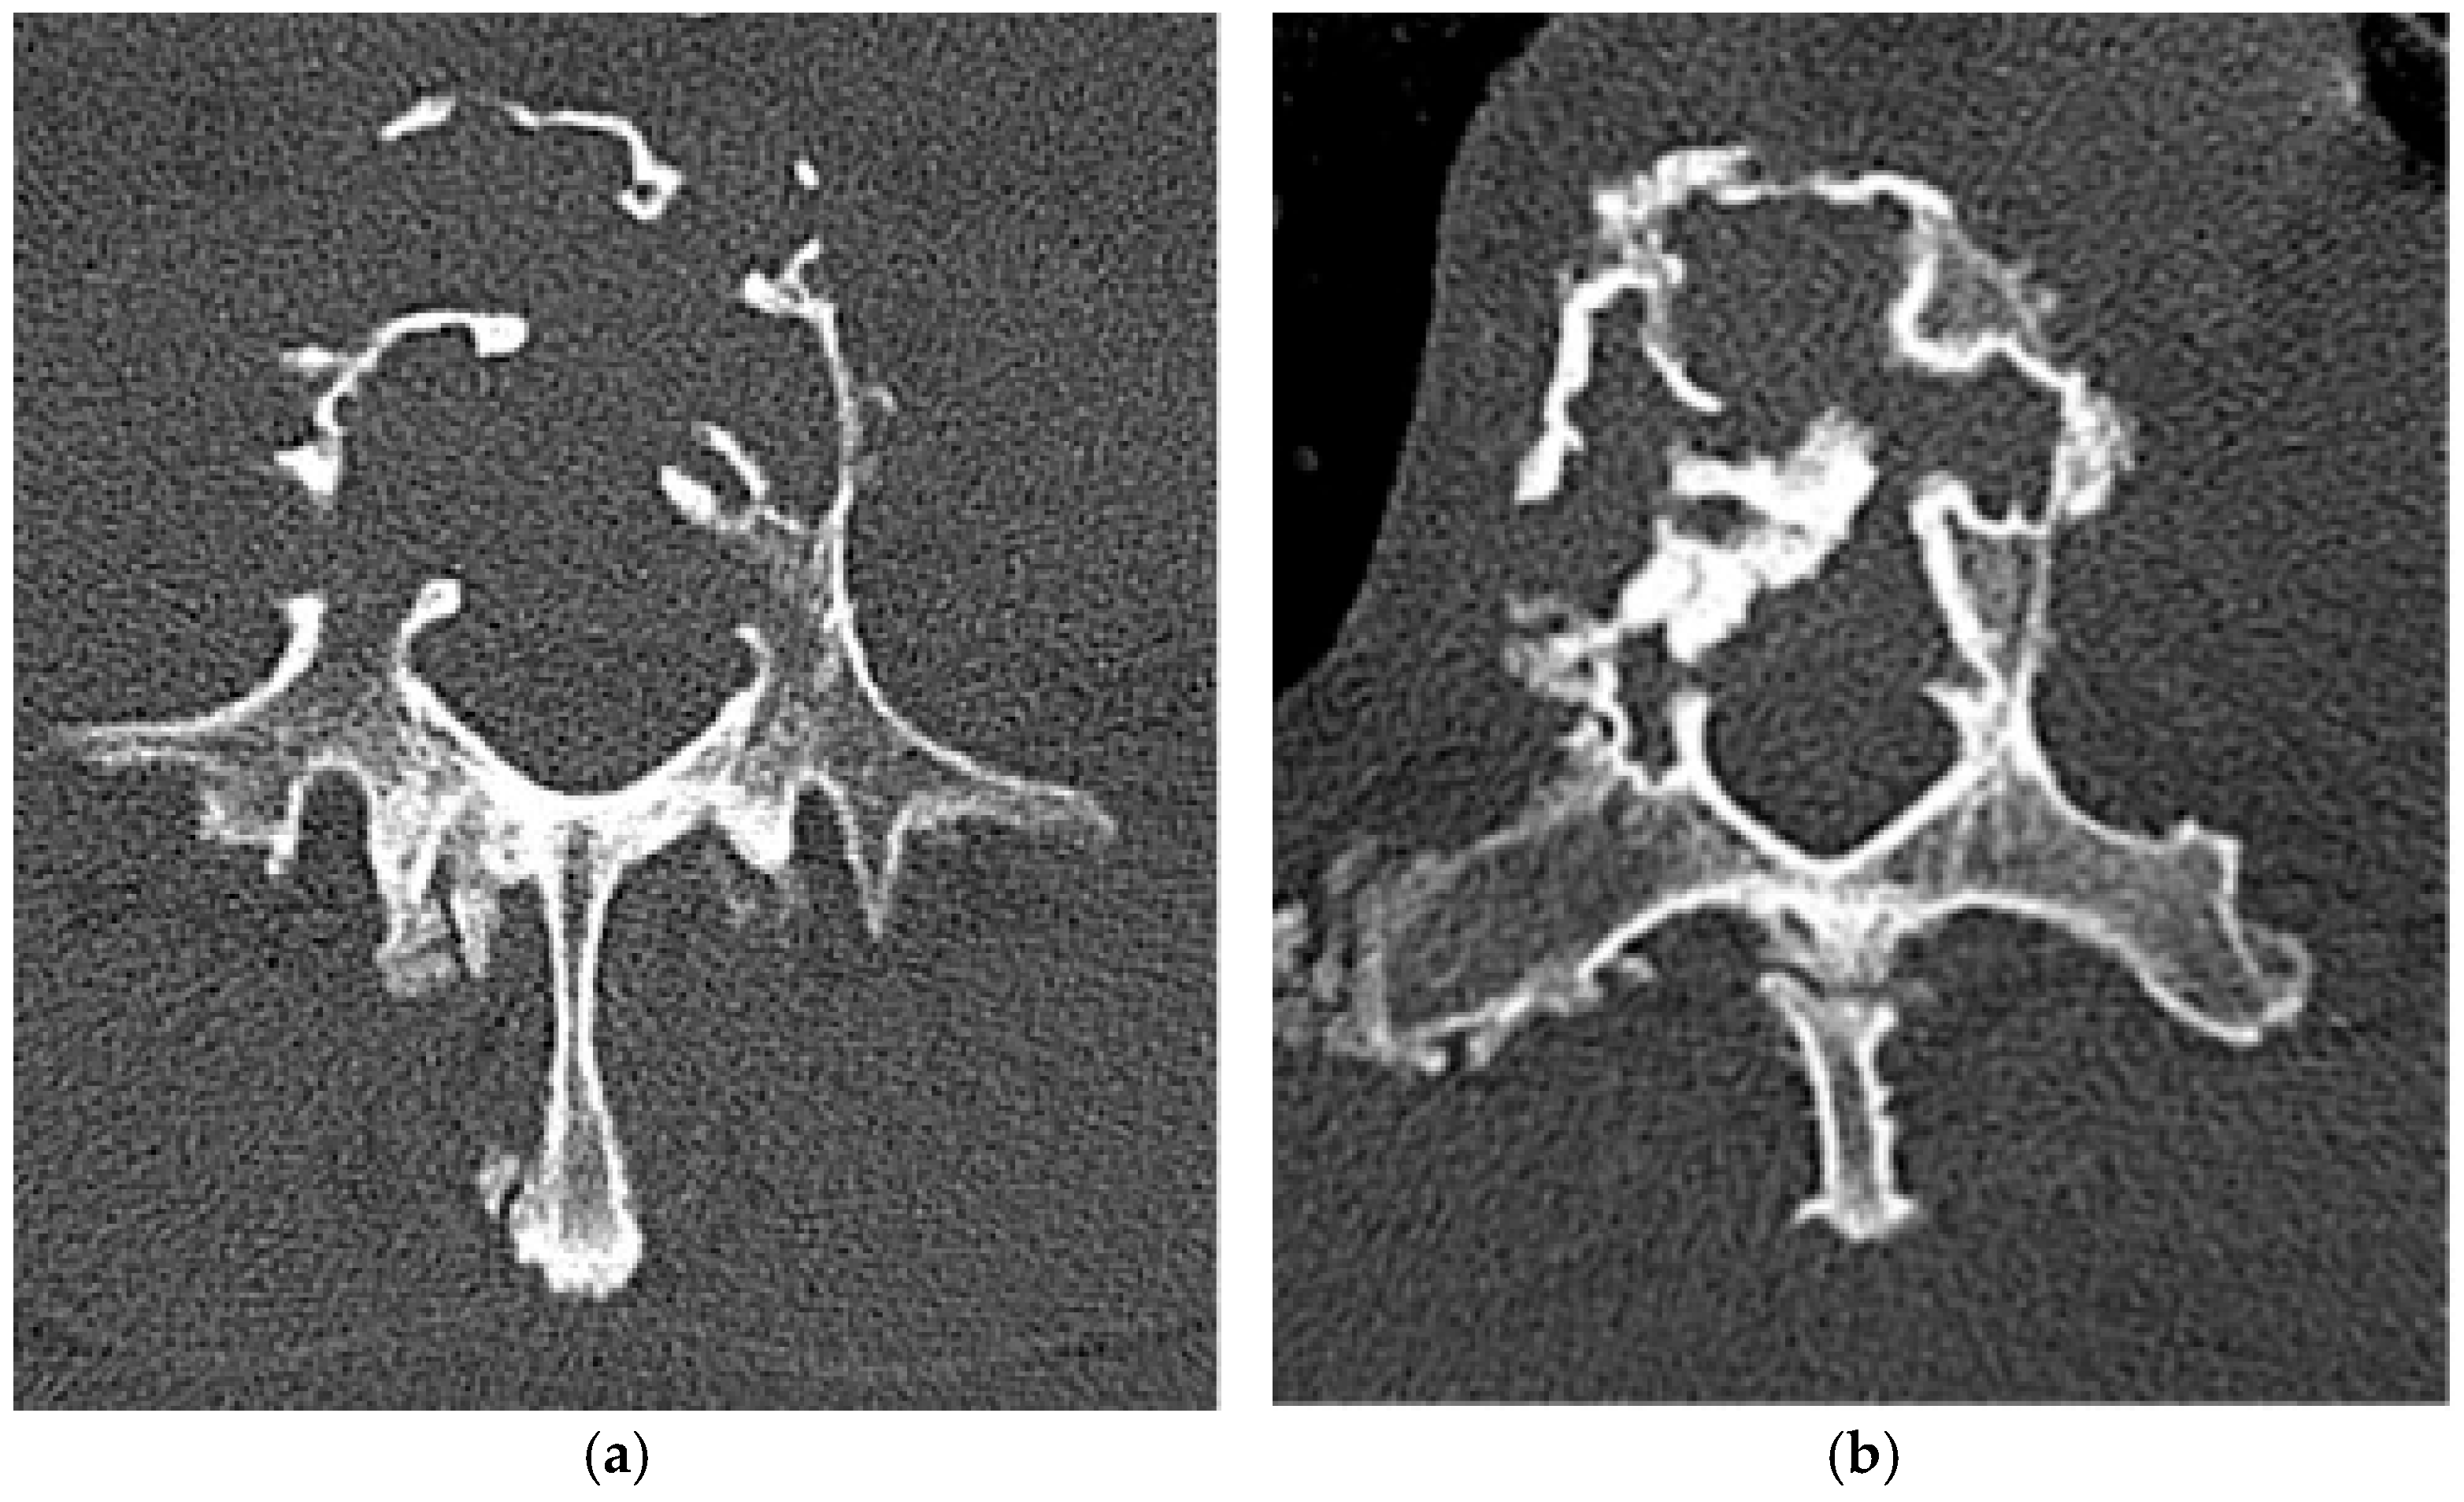

Paget’s Disease